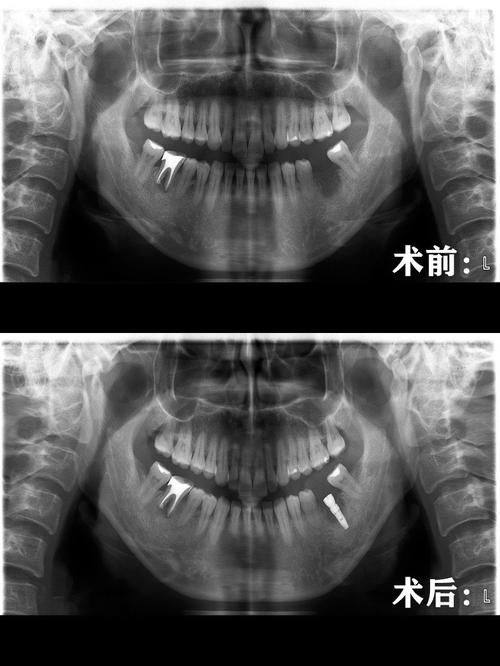

1. 种植牙:严秀院长擅长德国种植牙技术,主刀完成的手术超过2000台,术后成效自然优美,深受患者信赖。她凭借丰富的经验和不错的技术,能够根据患者的具体情况选择合适的种植体,确保种植牙的稳定性和美观度。

3. 患者王先生,40岁,因牙齿缺失需要进行种植牙手术。王先生在了解到严秀院长在种植牙方面的专精能力后,选择了她进行手术。手术过程非常顺利,术后修复也特别快。王先生说:“严院长的技术特别厉害,手术过程中没有感觉到太多疼痛。现在种植牙就像自己的牙齿一样,使用起来非常方便。严院长还会定期回访我的修复情况,让我感受到了她的专精和负责。”